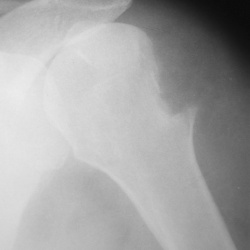

Женщина 60 лет пришла после приёма невропатолога сделать снимок плечевого сустава.

Мужчина 40 лет после падения с 3 этажа почувствовал болезненность в т\б суставах. Травма произошла около3 месяцев назад. Был сделан снимок.